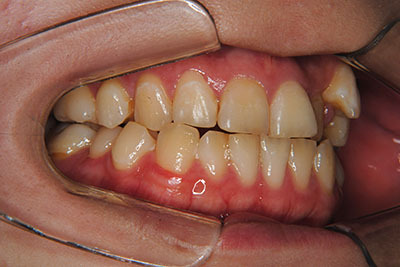

お口の中を診ますと、左上第二小臼歯が歯列の内側に生え、左上犬歯のスペースは全くない八重歯となっていました。検査結果から骨格的な不正はなく。上奥歯が前にずれたかみ合わせで前歯は合っていて出っ歯ではないので左右1本ずつ歯列からはみ出した状態であることがわかりました。上の奥歯を横の歯1本分後ろにずらすことは困難なので、右上中側に生えている第二小臼歯と八重歯である左上犬歯の次の歯=第一小臼歯の2本を抜歯し治療しました。

⑤抜歯部位:右上第二小臼歯、左上第一小臼歯